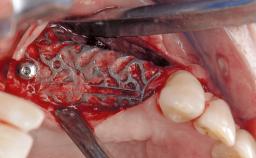

Resective Surgical Treatment of Peri-Implantitis Including Implantoplasty

In this case, Myroslav Solonko, Ignacio Sanz Sánchez and Mariano Sanz present a treatment that aims to eliminate exposed implant threads by modifying the implant surface, converting a moderately-rough surface into a smooth surface.